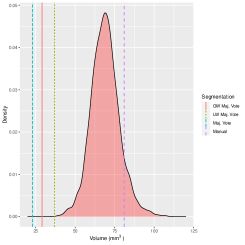

As already mentioned, only healthy brains are used as atlases. The systematic differences are not completely captured by atlas-target image dissimilarities. Despite accounting for image dissimilarity, there is a tendency for the established methods to over-segment the hippocampus. The Bayesian label fusion model facilitates explicit incorporation of the estimated gray matter pattern as a predictor. Our prior specification allows for the possibility that the tissue classes are incorrectly assigned in some places, but are mostly reliable. The effect of the gray matter segmentation as auxiliary information can be clearly seen by comparing it even with our own model in which this information is ignored but the model is otherwise identical. Figure 10 displays the posterior inclusion probabilities obtained without using the gray matter information, along with the results already presented for reference. Using only the intensity-similarity-weighted distance labels yields a Bayesian regression analogue to the other approaches that only weight by intensity similarity. The additional tissue class information is able to prevent oversegmentation of the diseased structure.

In practice, an anatomical structure is segmented to obtain important information such as its volume or average image intensity within the structure. In our case, segmenting the hippocampus is a step toward estimating its volume. If we only obtain a binary map, then the only way to estimate the volume is by summing the indicators. Doing so ignores many sources of uncertainty, including image pre-processing, registration error, biological variation, and rater variability. Monte Carlo sampling also facilitates estimation of a distribution of plausible volumes through , defined in Section 3. Figure 11 displays the marginal volume densities for the diseased brain of interest, both with and without gray matter included in the Bayesian label fusion model. Vertical lines indicate the manually-segmented volume and the volume estimates from the other procedures considered. The benefit of including the gray matter information is again evident with the improved agreement of the volume distribution with the manual segmentation. In this case, though, we see that even without the gray matter information the Bayesian model outperforms the three majority voting procedures.